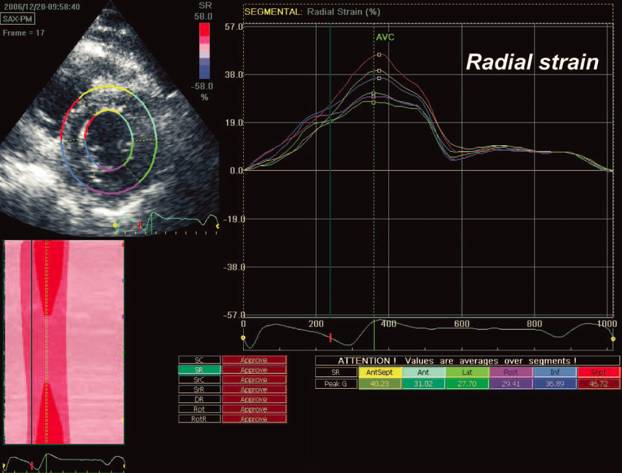

AF导管消融改善心功能

[16]